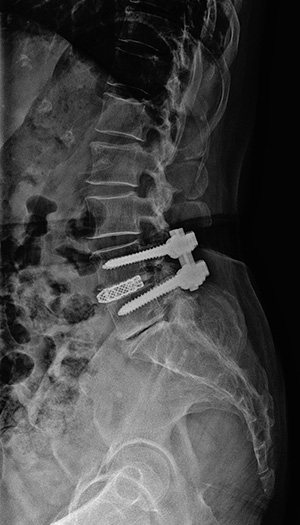

유합술 측면 X-ray